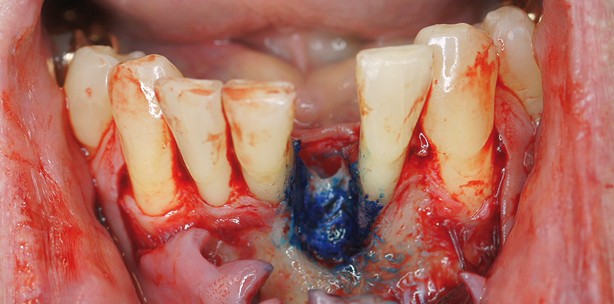

Nach zweitägiger Antibiotikavorbehandlung erfolgte der erste Eingriff. Es bestätigte sich nach Extraktion des Zahnes, dass die Extraktionsalveole eine komplette bindegewebige Auskleidung zeigte und keine Knochenoberfläche exponiert war. Es erfolgte eine lingual-interdentale und labial bis zu den Eckzähnen reichende intrasulkuläre Schnittführung mit zwei kleinen Entlastungsschnitten. Nach Ablösung des Mukoperiostlappens und gründlicher Kürettage der Extraktionsalveole erfolgte die ­fotodynamische Farbstoff-Lasertherapie mit dem Helbo-System, um eine absolute Keimfreiheit im Regenerationsbereich zu gewährleisten. Hierbei wird ein spezieller Farbstoff auf das Operationsgebiet aufgetragen und wirkt eine Minute lang ein. Die Bakterienhüllen werden angefärbt und durch Aktivierung des Farbstoffs mit einem speziellen Laser zerstört. Nun muss der Defekt ausgemessen werden, dies erfolgt mithilfe einer Trepanfräse. Erst danach wendet man sich der Entnahme eines Knochenrings aus der Kinnregion zu. Hierbei erfolgt zuerst die Anlage einer Implantatvorbohrung und dann die stufenweise  Aufbereitung eines Implantatbettes. Jetzt wird mit einer nächstgrößeren Trepanfräse die Implantatbohrung umfasst und ein Knochenring entnommen. Nachdem nun auch in der Regio 31 das Implantatlager präpariert wurde, wurde der Knochenring mit dem Implantat (BioHorizons 3,0mm/15mm Laser-Lok) im Defekt passgenau verankert. Zum Schutz vor übermäßiger Resorption wurde biphasisches Knochenersatzmaterial aufgelagert, der Regenerationsbereich mit einer Kollagenmembran abgedeckt und der Mukoperiostlappen spannungsfrei und speicheldicht vernäht. Dies erwies sich als recht einfach, da kein Weichgewebsdefekt vorlag. Labial wurde der gesamte Lappen zusätzlich koronal verschoben und fixiert. Um die Lücke zu kaschieren, wurde mithilfe der Schmelz­-Ätz-Technik eine Schneidekante in den Zwischenraum geklebt. Hierdurch wurden übermäßige Belastungen der Naht vermieden und Dehiszenzen verhindert. Nach zwei Wochen wurden die Nähte entfernt.